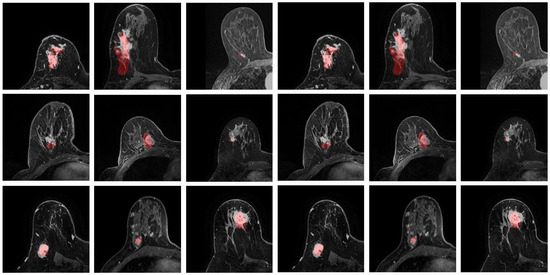

3.1. Model Performance

3.2. Registration Error

3.3. Correlation Analysis